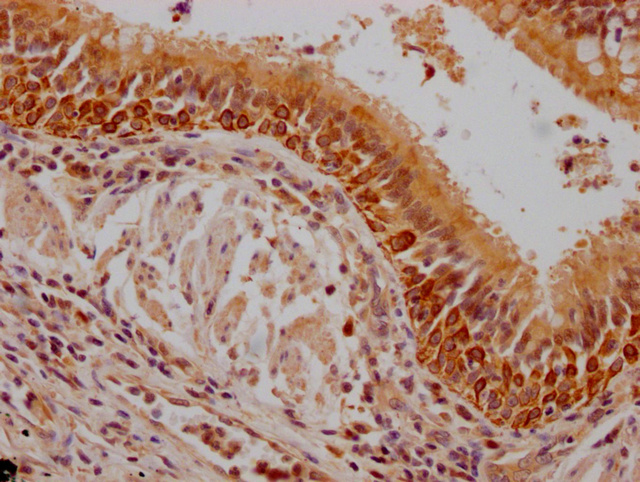

IHC image of CSB-PA614990LA01HU diluted at 1:200 and staining in paraffin-embedded human lung cancer performed on a Leica BondTM system. After dewaxing and hydration, antigen retrieval was mediated by high pressure in a citrate buffer (pH 6.0). Section was blocked with 10% normal goat serum 30min at RT. Then primary antibody (1% BSA) was incubated at 4°C overnight. The primary is detected by a Goat anti-rabbit polymer IgG labeled by HRP and visualized using 0.05% DAB.